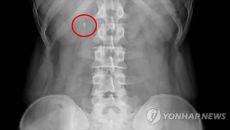

기온 오르고 활동 느는 봄철…옆구리 통증, 요로결석 신호일수도

(서울=연합뉴스) 권지현 기자 = 포근한 봄 날씨가 이어지는 가운데 갑자기 옆구리 등에 심한 통증이 느껴진다면 단순 근육통이- 2026-04-16 16:22

- 연합뉴스